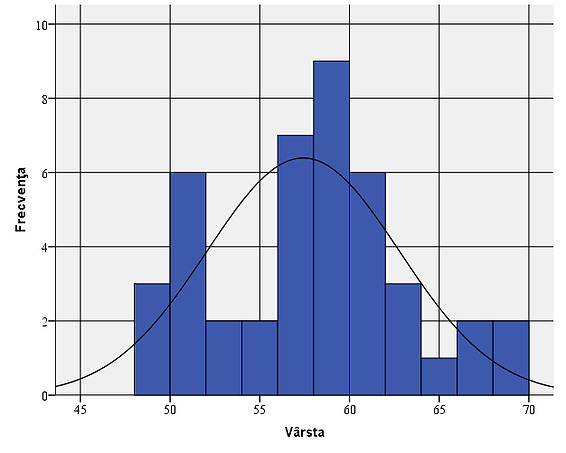

It is found that the average age of the individuals in the sample is 56.41 years. The subjects’ age deviates from the mean by plus or minus 19.58 years. The mode (modal value) is multiple and has the lowest value of 57 years.

This means that the most frequently encountered age in the patients in the sample was 57 years. The minimum age is 20 years, while the maximum age is 93 years.

We observe that we have a negative asymmetric curve, slightly tilted to the right (Skewness coefficient -0.252), with more extreme values to the left and platykurtic (Skewness coefficient -0.892), flatter than a normal distribution, with more values dispersed over a larger interval around the mean. The explanation for this distribution is given by a higher number of eye traumas that are more common in the male population compared to the female population, who opted for surgical intervention most frequently to improve the cosmetic appearance.

Figure 7: Gender distribution of the sample: , it is observed that men have a share of 65.1%, while women represent only 34.9%. Age: Looking at the sample from the perspective of the subjects’ age, it is found that their average age is 57.42. The age deviates from the average by plus or minus 5.36 years. The modal value (Mode) shows us that the age of 58 was the most common among the people in the sample.

Figure 8: Age variation within the sample:, it is found that their average age is 57.42. The age deviates from the average by plus or minus 5.36 years. The acrylic implant was used in 23 of the patients studied (53.5%), while the natural hydroxyapatite implant was used in 20 of the patients (46.5%).